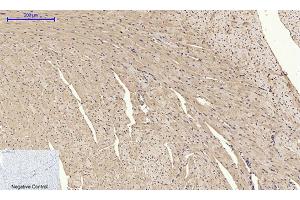

Western Blotting (WB), ELISA, Immunohistochemistry (Paraffin-embedded Sections) (IHC (p)), Immunofluorescence (IF)

BMP-2 Polyclonal Antibody

BMP-2 Polyclonal Antibody detects endogenous levels of BMP-2 protein.

Optimal working dilutions should be determined experimentally by the investigator. Suggested starting dilutions are as follows: WB (1:500-1:2000), IF (1:50-1:200), IHC-P (1:100-1:300), ELISA (1:10000). Not yet tested in other applications.